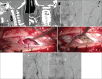

Patients and methods: In this report, we describe two unique cases of type I cervical spinal AVF, in which a radiculomeningeal artery forms an intradural fistula that drains into the ventral venous plexus.

Results: Both patients underwent surgical obliteration of the fistula with complete occlusion confirmed on postoperative angiography.